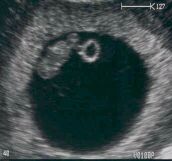

7 haftalık fetus

Bebeğinizin boyu bu haftada 8 milimetre olmuştur. Boyut ve şekil olarak bebeğiniz bu gebelik haftasında bir pirinç tanesi boyut ve şeklindedir. Kol ve bacak taslakları hızla gelişimini sürdürür.Beyin dokusu da gelişimini sürdürür. Lens (mercek), burun delikleri, barsaklar, pankreas ve bronşlar da yavaş yavaş belirgin hale gelmeye başlar.

Yanda 7 haftalık bir bebeğin ultrason görüntüsü yeralmaktadır. Siyah olan yuvarlak boşluk gebelik kesesi, içindeki ince uzun yapı embriyo, hemen sağında yeralan halka şeklindeki yapı ise daha sonra kaybolacak olan yolk sac (sak okunur) adı verilen yapıdır.